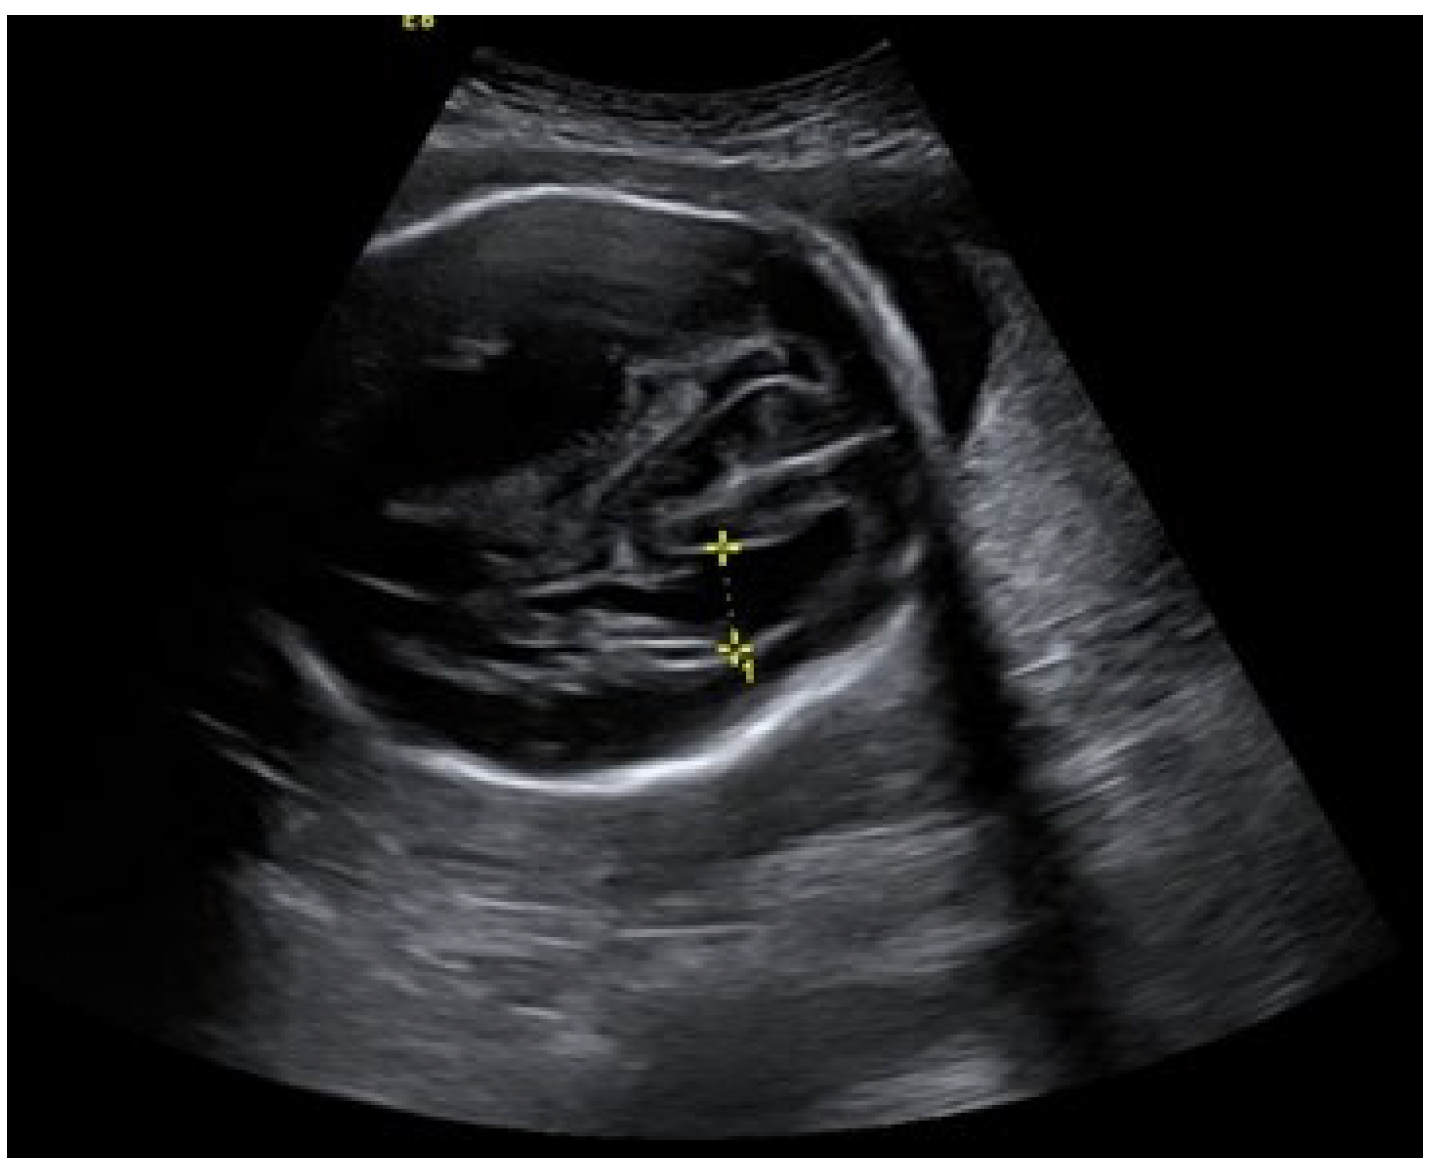

An ultrasound examination of the fetus was carried out through the abdominal wall, during which, pathological changes in the fetal brain were first observed (Figure 1, Figure 2 and Figure 3). A suspected tumor-like mass (2.75 × 2.16 cm) was seen in the anterior cerebral lobe of the right hemisphere, and dislocation of middle line and mild ventriculomegaly (1.38 cm) of the left lateral ventricle of the brain was present. Magnetic resonance imaging (MRI) of the fetal brain was carried out to establish the diagnosis (Figure 4).

Figure 1.

A suspected tumor in the right anterior fossa of the fetal brain.